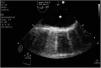

A patient is admitted to the hospital for an acute coronary syndrome complicated by a ventricular septal defect (VSD). Initially, treatment was performed with primary angioplasty and surgical correction of the VSD. During the procedure, the patient developed cardiogenic shock, requiring an intra-aortic balloon pump and a VA-ECMO. The VSD persisted despite treatment, leading to a heart transplant recommendation at a referral center. Prior to this, a CTA (computed tomography angiography) revealed an image consistent with an ascending aortic dissection (Images 1 and 2), resulting in the transplant being deferred. After reviewing the images at the transplant center, the aortic dissection was ruled out following assessment by transesophageal echocardiography of the aortic arch (Image 3), determining that the image was due to the confluence of ECMO flows, which eventually allowed the transplant to be performed.